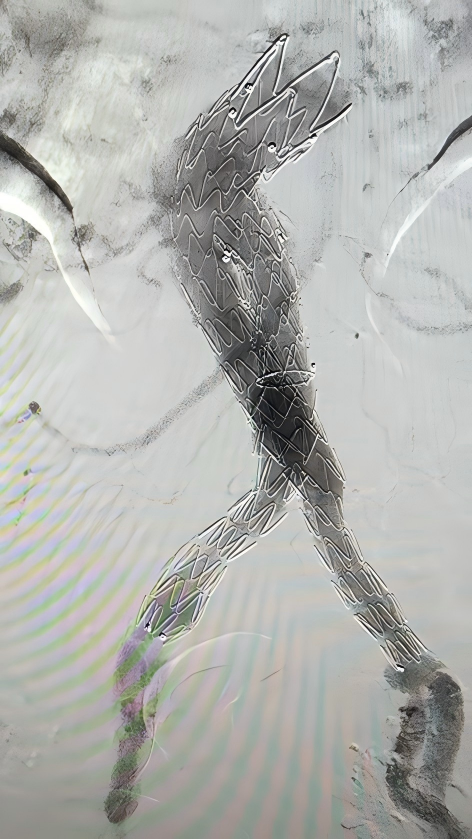

经过反复推演手术流程、模拟支架释放路径,并制定详细的围手术期管理计划(包括术前优化血压、血糖控制,术后预防感染、监测凝血功能等),团队最终确定了 「腹主动脉覆膜支架腔内隔绝术+髂动脉支架置入术」 的手术方案,简单来说,就是在血管内部植入特制的覆膜支架,像给破损的水管「打补丁」一样,精准修复了溃疡、隔绝了动脉瘤和夹层,并疏通了闭塞和狭窄的髂动脉。